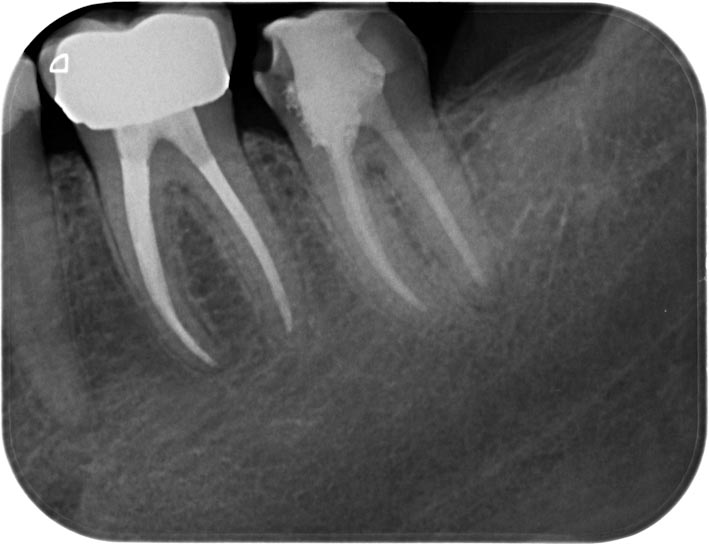

IR20130218-1 Veröffentlicht 1. Juli 2013 am 709 × 544 in Was zeigt das DVT ? (4) – Resorptionen- Die Antworten Teil 3 : Fall 2 WF Februar 2013